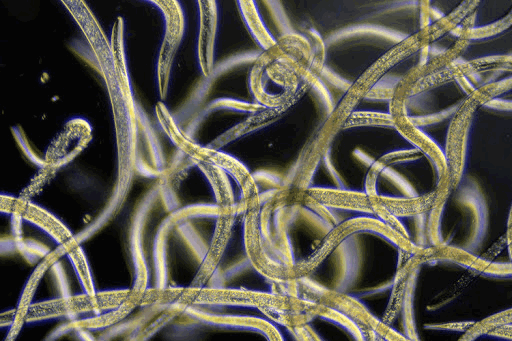

Болезнь Шагаса (американский трипаносомоз) - болезнь, вызываемая трипаносомами вида Trypanosoma cruzi (простейшие бесцветные организмы, имеющие веретенообразную форму).

Болезнь Шагаса вызывается трипаносомами вида Trypanosoma cruzi Штаммы Т. cruzi значительно различаются по кругу хозяев, географическому распространению, вирулентности и тропизму к тканям, а также по специфическим антисывороткам, зимотипам и типу рестриктивной ДНК.

Трипаносомоз - еще одно заболевание, вызываемое простейшими, а в частности простейшими рода Trypanosome.

Патогенными для человека являются T.brucei и T.cruzi, которые занимают различные территории и передаются разными насекомыми.

Для диагностики трипаносомоза используется световая микроскопия крови (тонкий или толстый мазок) или пунктата лимфоузла. Концентрация трипаносом в крови часто низкая, поэтому различные концентрационные методики увеличивают чувствительность диагностических методов. Серологической обследование часто неинформативно.

Для диагностики во время острой фазы болезни информативен анализ тонкого и толстого мазков крови, микроскопия окрашенных препаратов пунктата лимфоузлов. Напротив, для латентной инфекции или хронической болезни характерно небольшое количество паразитов в крови, в связи с чем могут быть использованы методы концентрации. Серологические исследования могут использоваться как скрининговые, положительный результат требует дообследования.

Микроскопическое исследование венозной крови методом концентрации на возбудителей филяриатозов и трипаносомозов (А26.05.010.s01)

Микроскопическое исследование крови методом толстой капли на возбудителей филяриатозов, трипаносомозов (А26.05.010.s02)